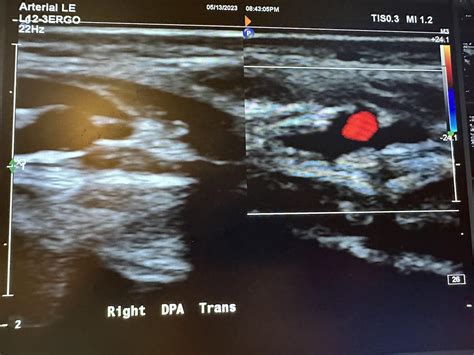

When manual palpation proves insufficient, clinicians turn to more sensitive diagnostic tools. The most common is the handheld Doppler device. By applying conductive gel to the skin and placing the Doppler probe over the expected location of the Arteria Dorsalis Pedis pulse, the healthcare provider can listen for the audible sound of blood flow. This method is highly effective at differentiating between a truly absent pulse and one that is simply difficult to palpate due to edema or anatomical variance.